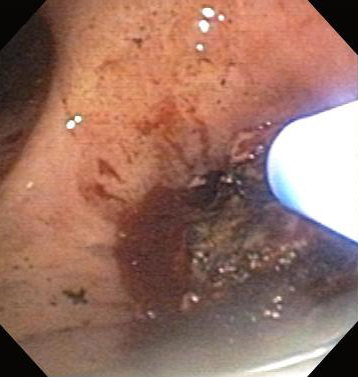

Бронхоскопическая терапия для обструкции нижних дыхательных путей правого главного бронха: аргоноплазменная коагуляция

Из коллекций Хосе Фернандо Сантакруза, дипломированного врача, члена Американской коллегии специалистов в области торакальной медицины, DAABIP, и Эрика Фолка, дипломированного врача, магистра наук; используется с разрешения